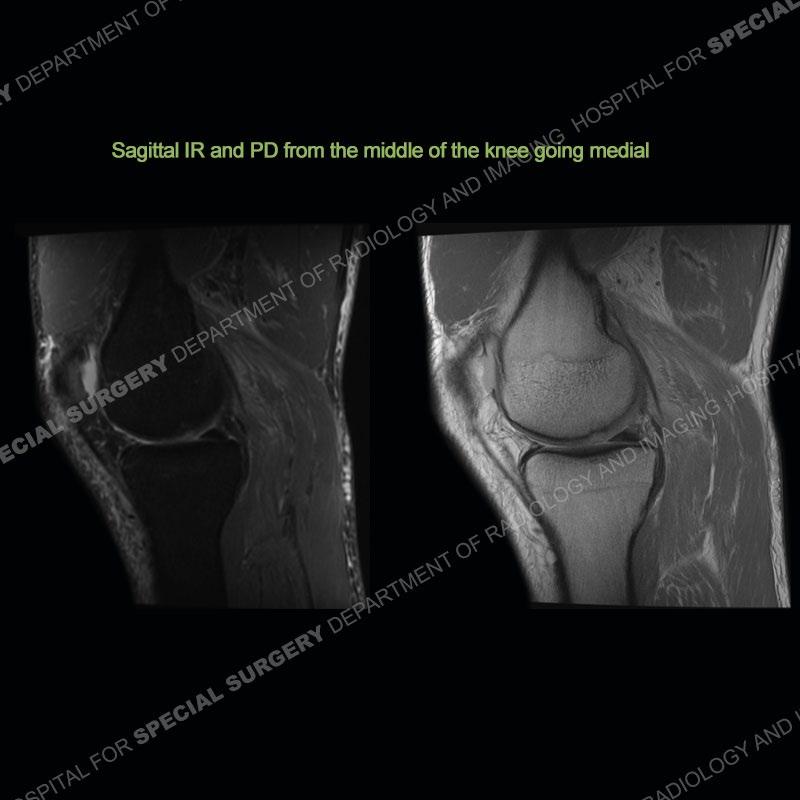

Findings

The radiographs show degenerative change of the medial compartment and a varus knee, but they are not germane to this case. No acute bony injury is present. The MRI shows edema of the posterior medial knee/soft tissue and a focal area of a partially disrupted low signal structure. The details are kept at a minimum in the findings of this case on purpose.

Diagnosis: Partial Disruption Medial Head Gastrocnemius (MHG)

The findings were kept purposefully vague as identifying the structures early on takes away a lot of the diagnosis. An uncommon entity and one of which we do not see a lot. Enthesopathic changes and tendinosis are seen as are distal MHG injuries, but proximal tears are rarely present. This case highlights a number of points. One, it almost always comes down to anatomy. Perhaps not a structure we normally spend too much time on, except save for diagnosing a Baker’s cyst, but knowing where this structure and all structures exist in all three planes is imperative. Second, when you think you are making a “call” or finding that you have never made before, step back and think is this just the abnormal presentation of a common pathology. That situation arises much more frequently. Third, if you look at it once, twice, and probably a third time and are confident in your odd or very rare diagnosis, stick to your guns. Especially, when it comes down to anatomic structures, the proof will be in the images.

Fourth, use all imaging planes and different pulse sequences to make your diagnosis. The edema highlighted in this case can be seen as the obscuration of fat on the PD images but is much easier to perceive as the high signal on the IR pulse sequences. The actual disruption of the MHG myotendinous junction is only able to be seen on the axial images. On the sagittal and coronal images, we get a sense something is wrong but hard to be exact. Lastly, when you look at a study and something just seems off (as I would say the sagittal and coronal images do with that dark band of tissue posteriorly), listen to yourself and go through the study slowly and meticulously. Most of the time you will find you were right, and something indeed is present.